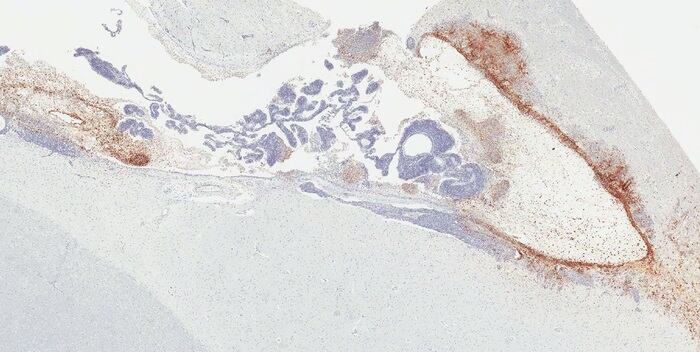

«El nuestro es el primer estudio que revela el escondite de la persistencia del virus del ébola en el cerebro y la patología que causa la posterior enfermedad mortal relacionada con el virus del ébola en el modelo de primate no humano. Descubrimos que alrededor del 20 por ciento de los monos que sobrevivieron al ébola tras el tratamiento con anticuerpos monoclonales seguían teniendo infección persistente, específicamente en el sistema ventricular del cerebro, en el que se produce, circula y contiene el líquido cefalorraquídeo, incluso cuando el virus del ébola se había eliminado de todos los demás órganos», explica el líder de la investigación, Kevin Zeng.

En particular, dos monos que inicialmente se recuperaron del ébola tras el tratamiento con anticuerpos monoclonales presentaron una recurrencia de los signos clínicos graves de la infección y sucumbieron a la enfermedad. La inflamación severa y la infección masiva por el virus del ébola estaban presentes en el sistema ventricular del cerebro; no se encontró ninguna patología evidente ni infección viral en otros órganos.

Durante los últimos años, el equipo de Zeng ha realizado estudios sistemáticos sobre la persistencia del virus utilizando como modelo a primates no humanos supervivientes. Esa investigación demostró que el virus, a pesar de haber sido eliminado de todos los demás órganos, puede esconderse y persistir en regiones específicas de órganos inmunes privilegiados, como la cámara vítrea de los ojos, los túbulos seminíferos de los testículos y el sistema ventricular del cerebro, según se informa en este estudio.